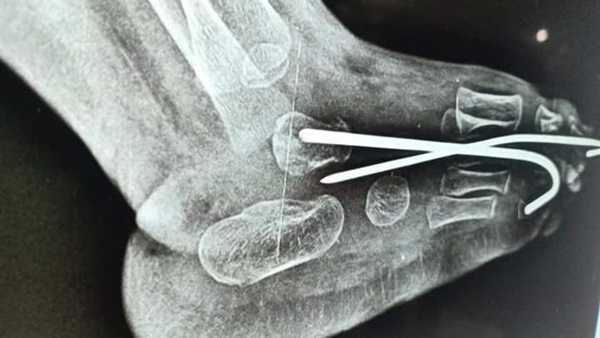

حيث قام الفريق الطبي بمستشفى حوش عيسى بقيادة الدكتور نصر القزاز رئيس قسم العظام ورئيس الهيئة الطبية و الدكتور محمود عطية مقاوي مدرس التخدير بجامعة الاسكندرية والفريق المعاون تحت إشراف الدكتور محمود طلحة وكيل الوزارة والدكتور حمودة الجزار وكيل مديرية الصحة بتقويم وتصليح الكاحل الخلقي العمودي Congenital Vertical Talus والذي ينتج عنه اعوجاج شديد جداً في القدم والكاحل لطفل يبلغ من العمر عاما.